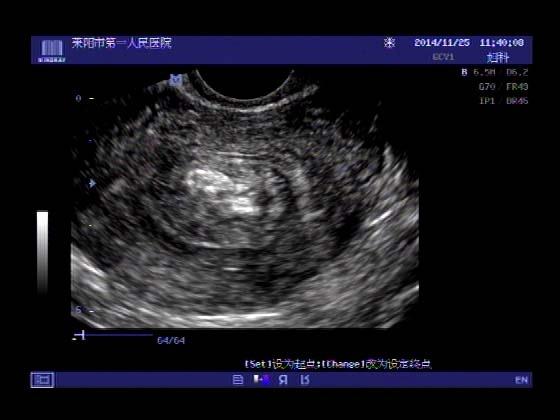

超声入门贴379---------粘膜下肌瘤(阴超的魅力)

女,43岁,月经量多3个多月,加重一个月

外院彩超检查提示:子宫后肌壁略高回声团------肌瘤?息肉?,盆腔少量积液

今天来我院检查:

巧妇难为无米之炊,经腹部超声确实很难定,阴超一目了然,乡镇医院诊断水平的提高更迫切的需要高档仪器的引进!